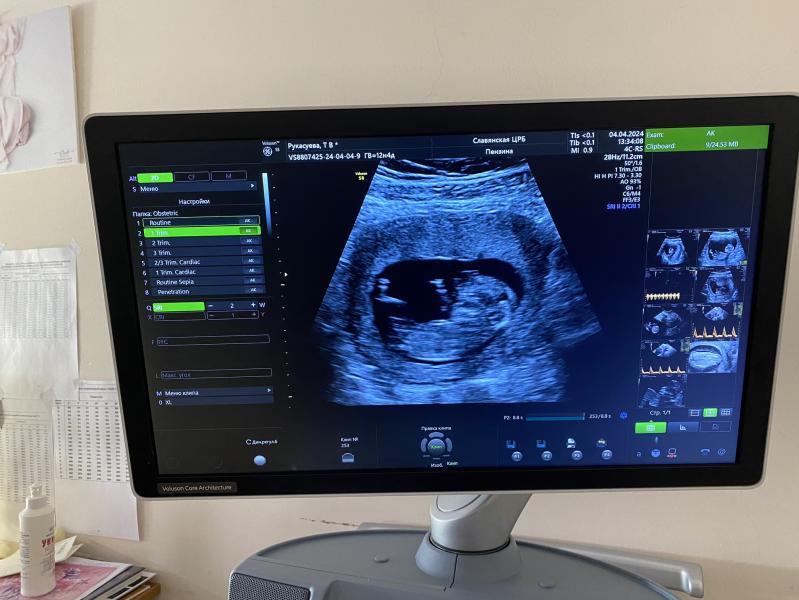

Кто видит пол?

Кто может разглядеть пол ?😅

Будет мальчик 😁☝️

Пол смотрят между ног)) и не так рано

Девочка. Вроде как параллельно всё))

там что-то похожее на яички

а может быть и пуповина😃

50/50

@grigorenkotanya99, нам объяснила узист, что у мальчиков бугорок повыше в том месте, у девочек прям покатый вниз

@grigorenkotanya99, да не за что)) но на таком сроке все равно сложно еще понять. Да и вот недавно девушка писала, как ошиблись даже в 15 Нед, хотя сейчас это как-то маловероятно)